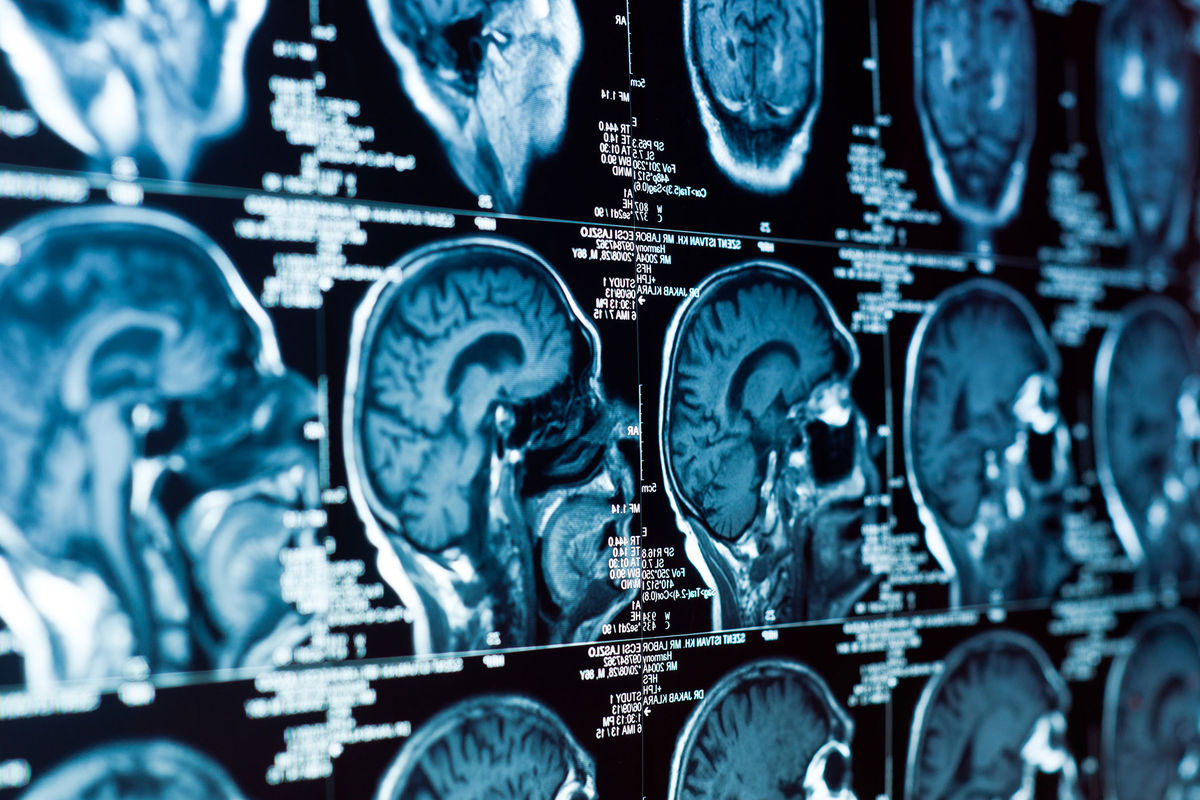

Ткань из области передней части мозолистого тела — одного из самых насыщенных миелином участков мозга — проанализировали методом одноядерного РНК-секвенирования. Это позволило отследить активные гены в тысячах отдельных клеток.